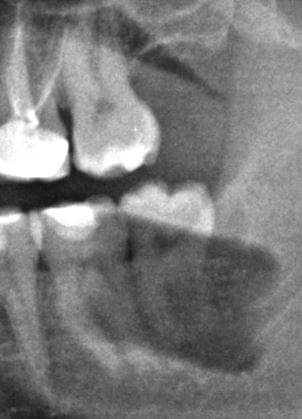

En Agosto me extrajeron la última muela del juicio (inferior derecha). Era la que mejor tenía y por eso se quedó para la última. No me molestaba en absoluto pero mi odontólogo me recomendó sacarla porque estaba totalmente rodeada de encía y hacía difícil su limpieza, riesgo de infecciones, etc. La extracción apenas duró 1 minuto y el odontólogo me comentó que estaba muy "agarrada" pero que todo fue bien. Pasaron los días y tenía mucho dolor que se irradiaba hacia el cuello. Me comentaron en la revisión que tenía una alveolitis y se terminó pasando a los 15-20 días. Tras esto y voy al meollo de la cuestión, me noté en la parte interior de la mandíbula como un bulto a la altura del alveolo de la muela extraída. Si pasas el dedo por la línea de la mandíbula interior, al llegar a ese punto se nota como un resalto en el hueso. No me produce un dolor enorme, pero sí una molestia continuada en esa zona, como si tuviera algo por dentro presionando la encía. Volví al dentista y me dijo que era el hueso de la mandíbula y que con casi toda seguridad se reabsorbería con el paso del tiempo, que no le diera importancia. Que en el caso de no re absorberse me abrirían la encía y lo pulirían sin problema para que la línea de la mandíbula volviera a estar lisa. Han pasado 6 meses y tras no ver progreso alguno y continuar con molestias constantes en la zona del bulto volví al odontólogo que comprobó que el agujero que había dejado la muela ya estaba cubierto completamente y me hizo una radiografía en la que se veía que todo estaba correcto, el hueso ya se había formado donde antes estaba la muela. Le pregunté si ese bulto lo había tenido siempre o me había salido a raíz de la extracción. Me explicó que a veces pasa en las extracciones que el hueso mandibular se puede astillar al hacer fuerza para la extracción, y que seguramente eso era lo que había pasado. Me propuso limar el hueso, creo que lo llamó “regularizar el reborde alveolar a nivel del 48”, pero esta vez me lo puso peor que 6 meses atrás donde parecía algo rutinario, me advirtieron que no era tan simple al pasar el nervio lingual por debajo, que había ciertos riesgos. Acepté con tal de quitarme esta molestia continua. La cirugía fue bien, pero han pasado 2 semanas y noto que sigo teniendo resalto a la altura del alveolo (menos que antes) y me sigue molestando. He ido a la revisión y me han dicho que es normal, que deje pasar tiempo y seguro que se regulariza sólo. Sobre todo me dicen que no me toque el resalto con la lengua, algo casi imposible, ya que se me va constantemente a ese punto, no puedo evitarlo. Empiezo a estar un poco angustiado y bastante nervioso. ¿Me recomendáis que siga esperando varios meses más a ver si mejora sólo tras esta última cirugía o deberían volver a abrir la encía y limar el hueso más? ¿Es verdad que el reborde alveolar o bulto que noto en la encía con el paso del tiempo irá desapareciendo?